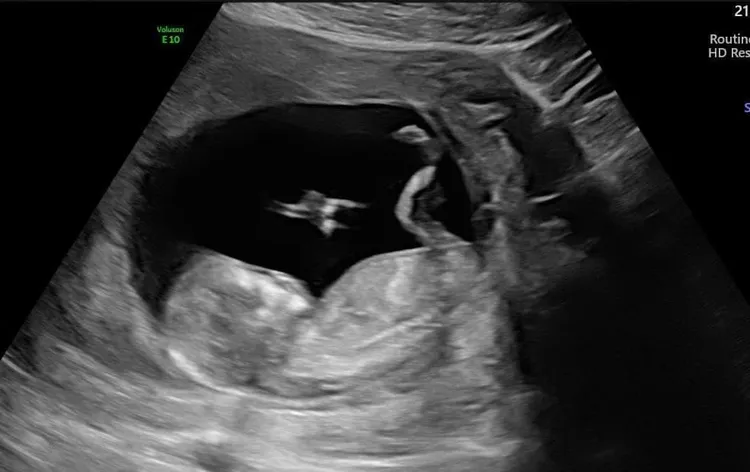

廖科溢無視風波在臉書曬出產檢超音波宣布,「頭好壯壯,滿三個月,終於可以說了!辛苦了!」